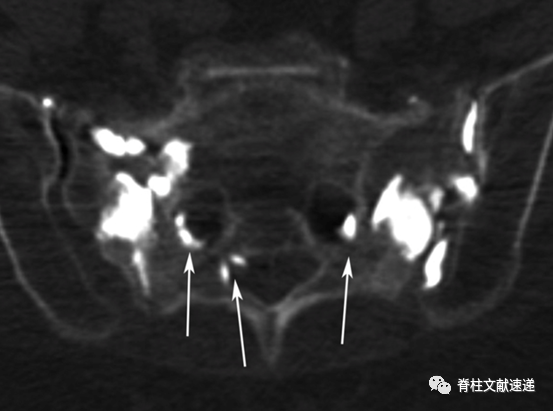

骶骨成形术手术操作:透视下将13G穿刺针置入骶后孔和骶髂关节中间的骶骨翼,与骶髂关节成45度,侧位上位于骶骨正中,一侧可以置入2-3根穿刺针,以保证骨水泥分布均匀,注入骨水泥时正位片上观察,避免骨水泥向内侧延伸,如下图所示。手术操作较胸腰椎椎体成形容易。